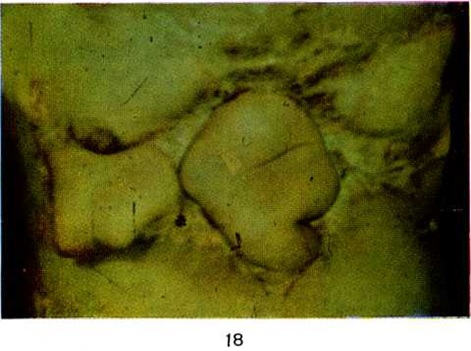

Рис. 18.

Та же область через 8 месяцев после иссечения краёв и дна язвы и поэтапного закрытия её с помощью мигрирующего стебля Филатова.